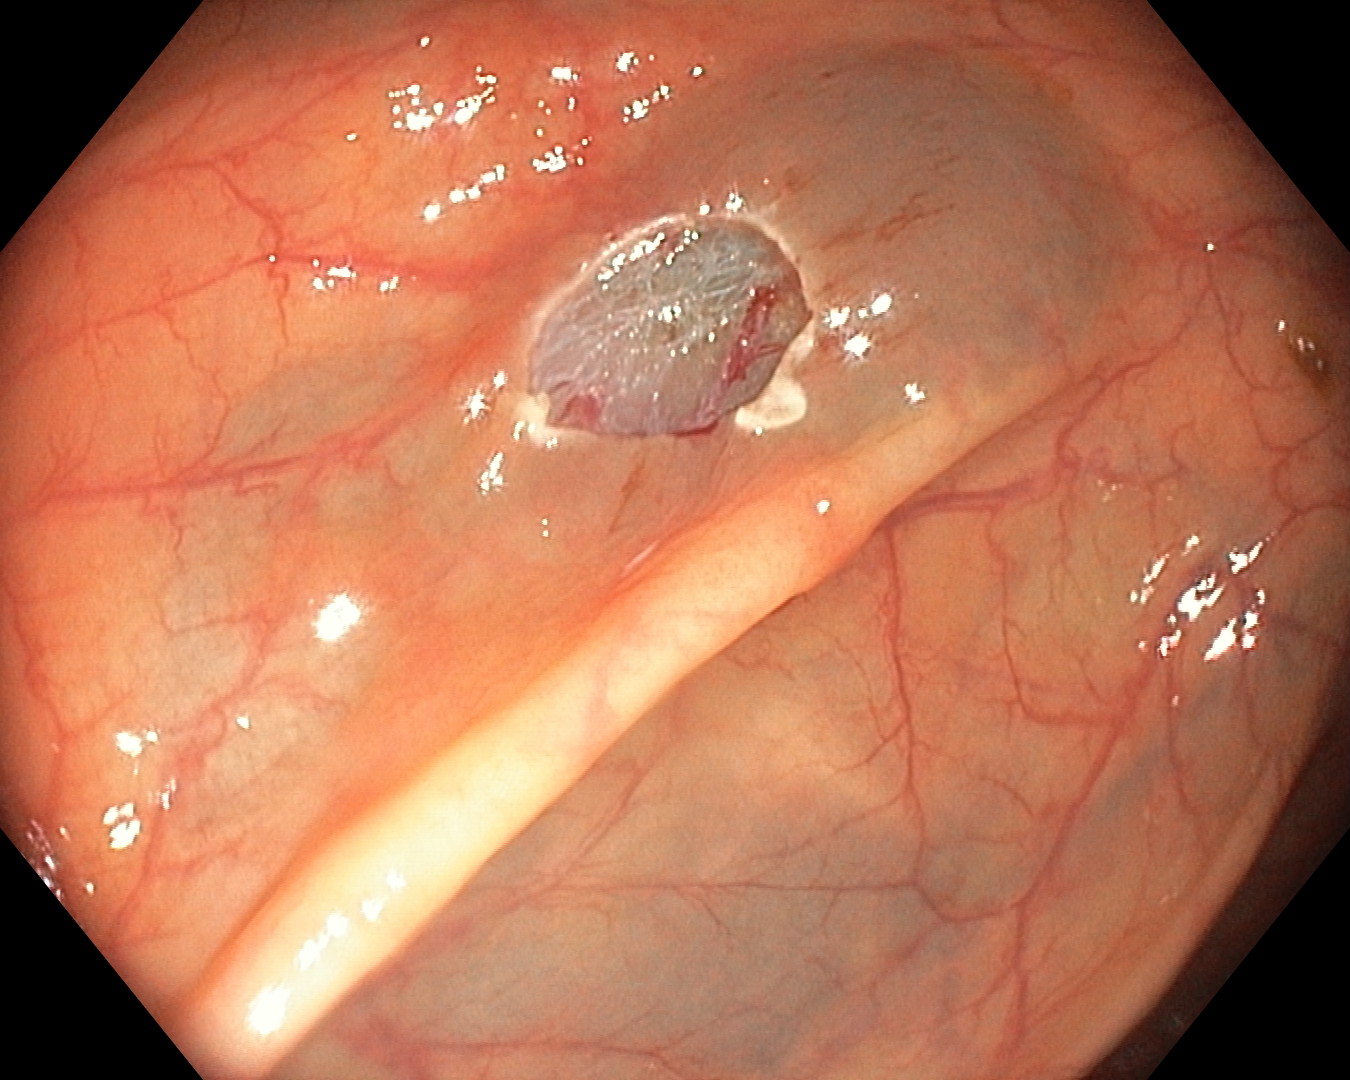

Bitno je napomenuti da su ove napredne slikovne metode (digitalno uvećanje slike i prikaz pod uskopojasnim spektrom), naročito korisne u endoskopskoj analizi polipa kolona. Ovdje u većini slučajeva nije potrebna dodatna patohistološka analiza, čime se ubrzava postupak dijagnostike, uz financijske uštede sa strane pacijenta

Prikaz polipa kolona pod normalnim svjetlom | Prikaz polipa kolona u uskopojasnom spektru |

Prikaz polipa kolona u uskopojasnom spektru s uvećanjem

| Resekcijsko mjesto nakon uklanjanja polipa (polipektomija) |